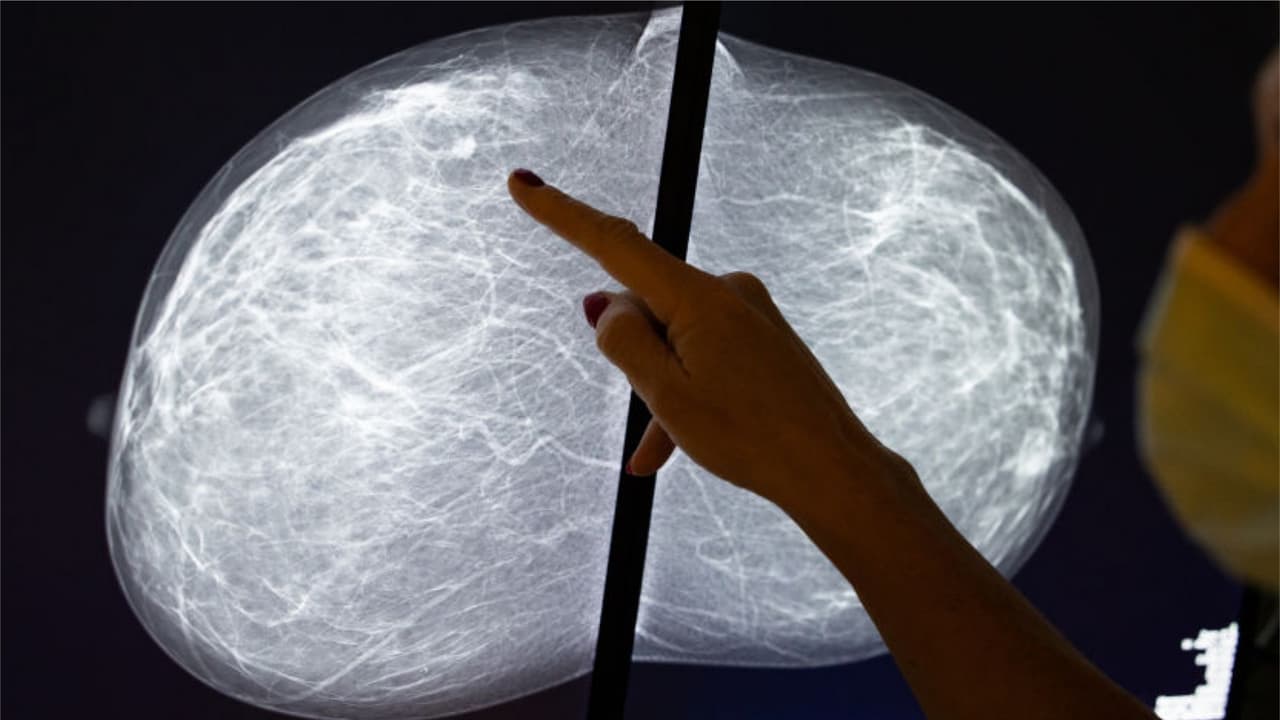

Según un reciente estudio publicado por la revista médica JAMA, casi 10 millones de exámenes preventivos se dejaron de hacer durante el 2020 debido a la pandemia. Por lo anterior, especialistas en el tema del Baptist Health South Florida pidieron a las personas retomar sus estudios de rutina. “La detección temprana hace la diferencia”, recalcó la doctora Jane Méndez, jefa de cirugía de senos del Instituto de Cáncer de Miami.